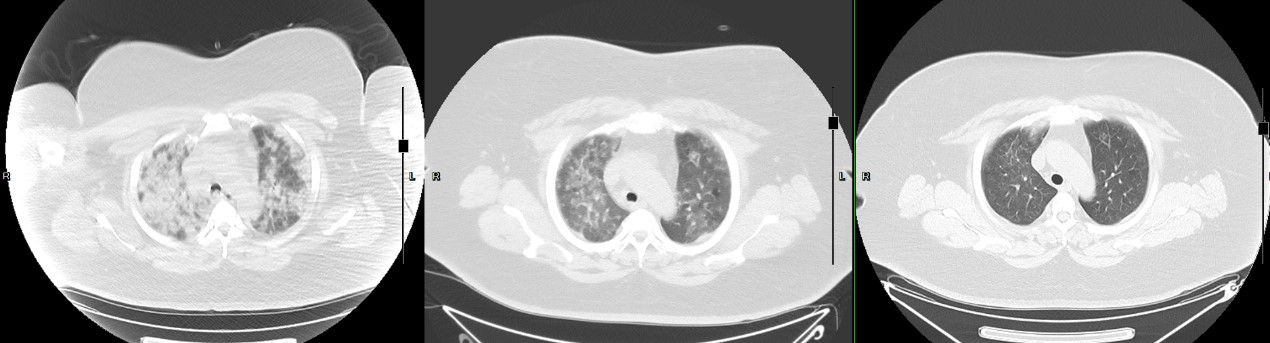

接到求助信息后,林育红主任迅速评估患者病情并联系了傅女士,向她介绍了科室情况,预留了治疗床位。这一通电话于傅女士来说,就如同黑暗中失去方向的人终于见到黎明的曙光,傅女士当下就联系120急救车将小卓转运到东北国际医院呼吸内科。此时的小卓,仅能端坐呼吸,高热不退,无法脱离吸氧,吸氧时的指脉氧只有76%,动脉血气结果提示氧合指数58.57mmHg,已经达到重度急性呼吸窘迫综合征的诊断标准,胸部CT结果见到肺部大片的炎性渗出影像,已经形成所谓“白肺”。小卓病情危重,严重缺氧,普通吸氧措施无法满足她身体需求,而她又有幽闭恐惧,不耐受面罩呼吸机治疗,呼吸科医生紧急为她进行经鼻高流量湿化氧疗,减少对面部压迫,不会出现幽闭感觉,接受度更高,舒适度更好,小卓终于可以顺利配合氧疗,氧合指标得到了改善,指脉氧可以维持在相对安全的90-93%。

患者的胸部CT变化

调整抗炎抗前病毒治疗方案后,小卓情况日渐好转,指脉氧和氧合指数稳步回升,再次复查胸部CT,肺部炎性病灶明显吸收,不再是“白肺”了!看着女儿可以脱离氧气在床边走动,指氧仍可以维持在95%以上,傅阿姨终于放下心来。后续,经治医生马医生又帮小卓联系了营养科门诊进行饮食指导,改善代谢状态;联系了中医科进行后续调整免疫力,改善特异体质。